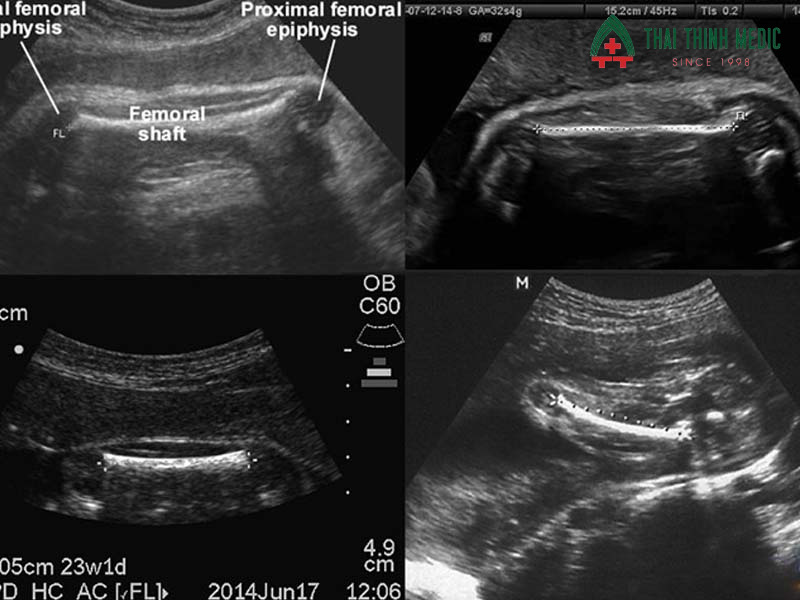

Ngoài CRL, NT, nhịp tim và túi thai, bác sĩ còn quan sát các chỉ số bổ sung như chiều dài xương đùi, kích thước đầu và bụng, nhằm đánh giá toàn diện sự phát triển của thai. Các chỉ số này giúp phát hiện sớm tình trạng chậm phát triển hoặc bất thường, từ đó lập kế hoạch theo dõi và can thiệp kịp thời.

Chiều dài xương đùi